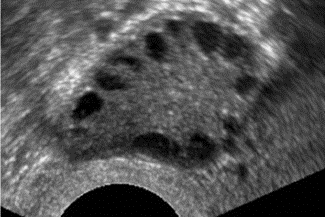

AFC erhöht bei PCOS, ACF > 15